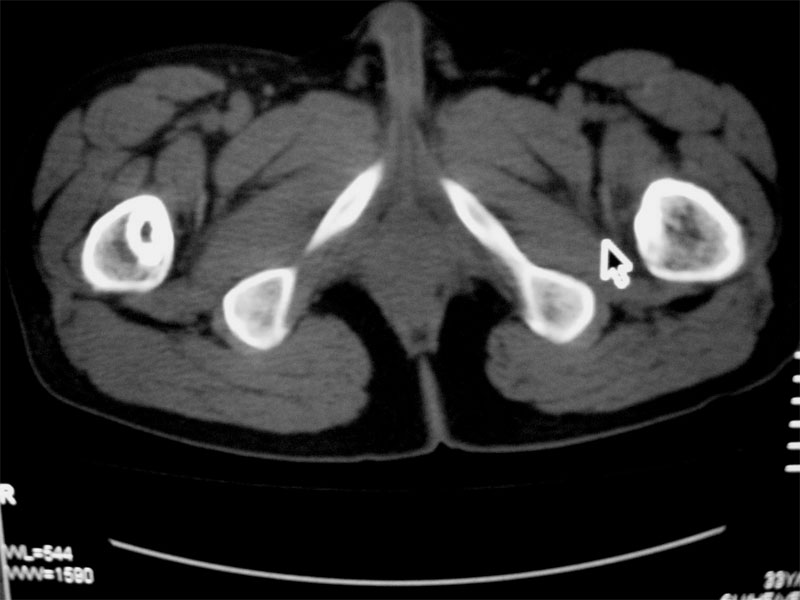

标题: CT16604:男32岁,左髋关节处疼痛月余 [打印本页]

标题: CT16604:男32岁,左髋关节处疼痛月余

左侧髋关节少量积液.上传骨窗

建议提供骨窗资料

考虑左股骨头缺血性坏死;右股骨上段良性骨肿瘤,考虑成软骨细胞瘤可能。建议上传骨窗。